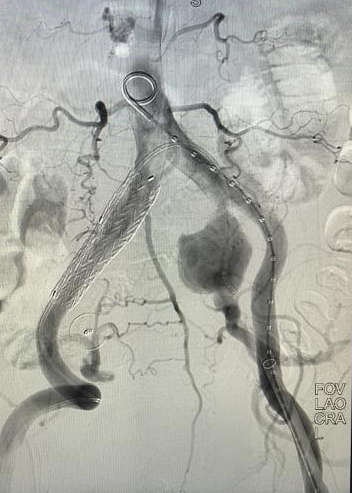

心脏问题解决后,治疗的“接力棒”交到了血管外科团队手中。团队预先在腹主动脉支架上为副肾动脉开窗并标记,随后在术中精准定位,将导丝导管通过开窗口超选入副肾动脉并成功植入支架,最终造影显示,腹主动脉瘤被完全隔绝,副肾动脉血流通畅,且无内漏。术后,患者肾功能维持良好,平安出院。

10月30日术前 00_00_00-00_00_30.gif

10月30日 邓先生(术后).gif

患者术前(左)、术后(右)DSA检查结果对比